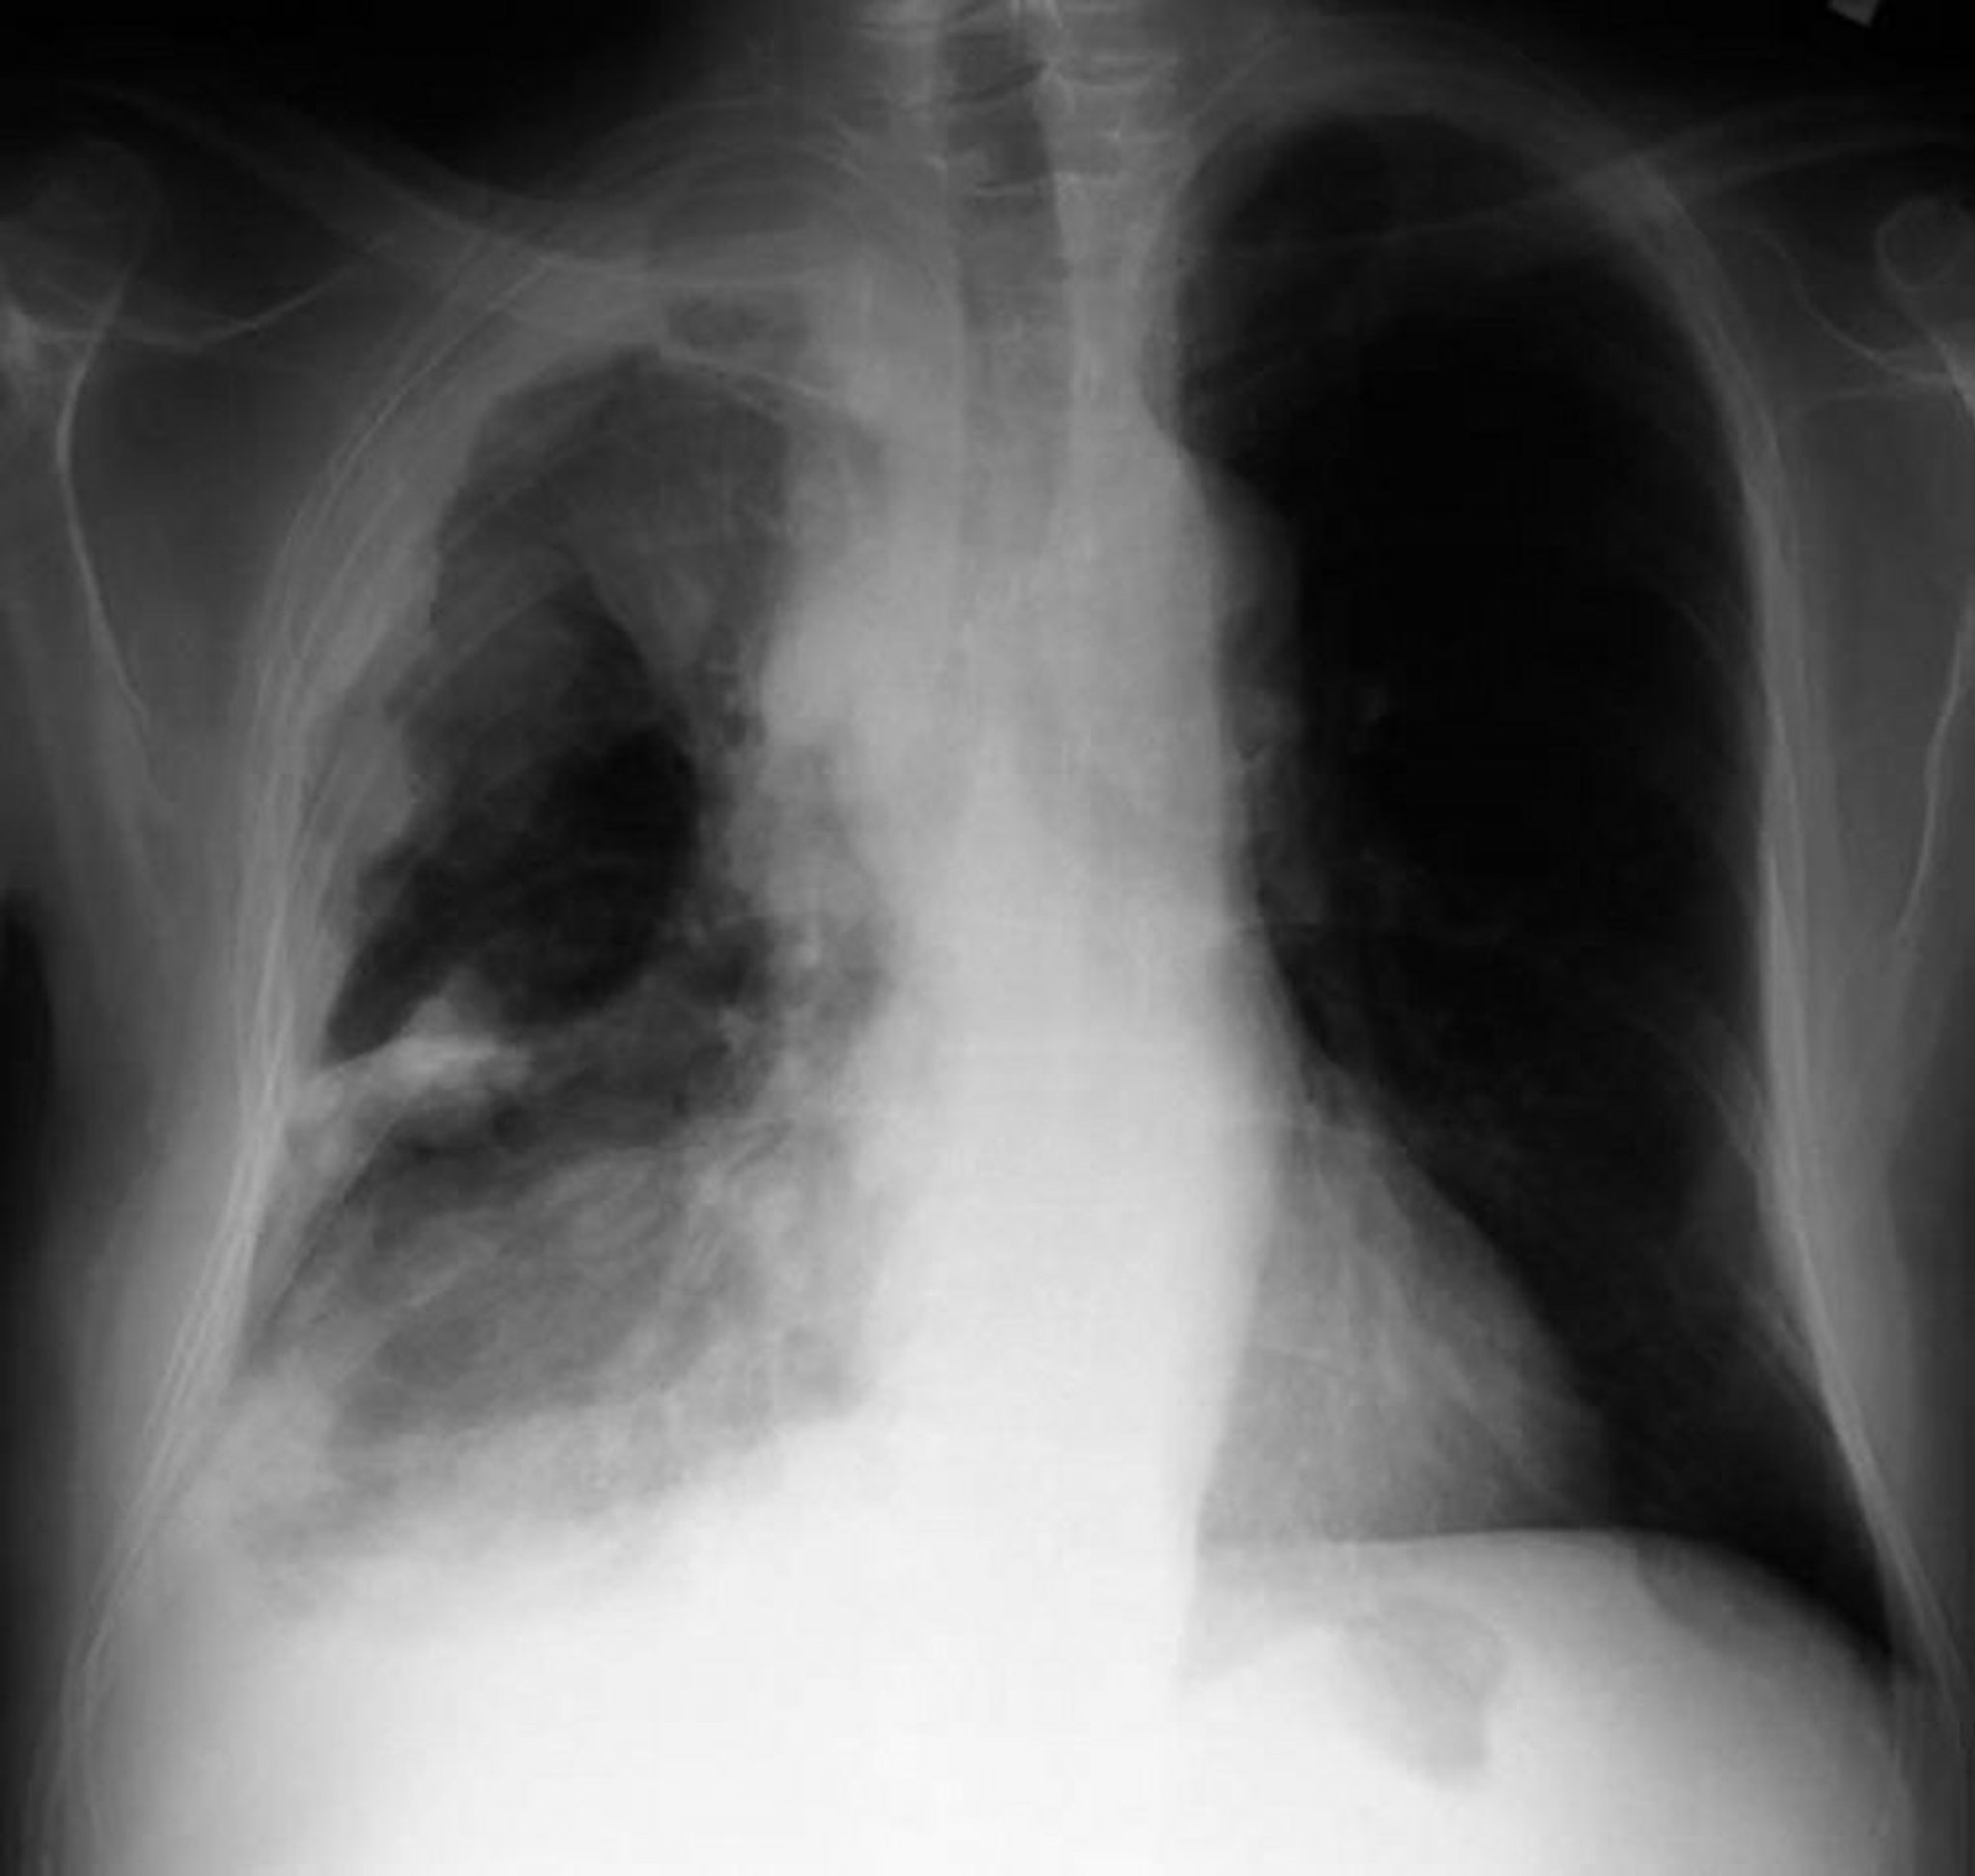

Chest x-ray in a patient with pleural mesothelioma shows pleural thickening with nodular masses on the parietal pleura.

By permission of the publisher. From Huggins J, Sahn S. In Bone's Atlas of Pulmonary and Critical Care Medicine. Edited by J Crapo. Philadelphia, Current Medicine, 2005.